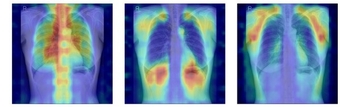

사진】흉부X선에서 파운데이션 모델이 골다공증 판독을 위해 주목한 영역을 시각화한 이미지

연구팀은 여기에 더해 AI가 실제로 어떤 뼈를 근거로 삼아 판단하는지까지 확인할 수 있도록 ‘설명 가능성’ 평가 체계를 설계했다. 뼈를 모두 가린 상태에서 특정 뼈 부위를 추가해 성능이 얼마나 향상하는지 확인하는 ‘차단 분석 방식(Δbone)’과 Grad-CAM으로 나타난 AI의 주목 영역이 실제 뼈 위치와 얼마나 일치하는지를 계산하는 ‘유의성 지도 방식(IoUbone)’을 통해, AI가 임상적으로 중요한 뼈 구조를 근거로 판단하는지를 정량적으로 검증했다.

그 결과, DINOv2 모델에 LoRA 방식을 적용한 모델이 AUC 0.93(95% CI 0.92–0.94)로 가장 높은 예측 성능을 보였다. 이 모델은 뼈 구조 활용도가 가장 높고, 주목 영역의 타당성에서도 우수해, 예측력과 설명 가능성이 균형 있게 확보된 최적 모델로 평가됐다.